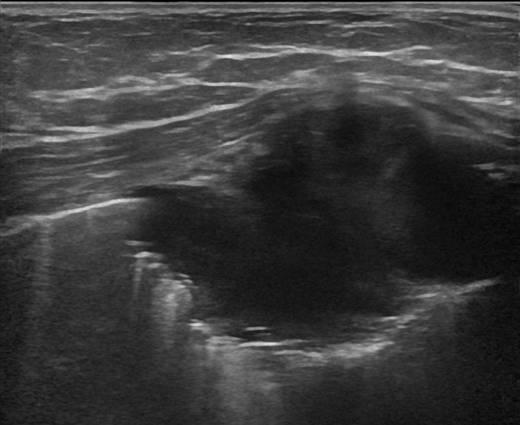

Di căn thành ngực

» Thông tin: Nam giới – 64 tuổi.

» Lâm sàng: Khối thành ngực / K vòm.